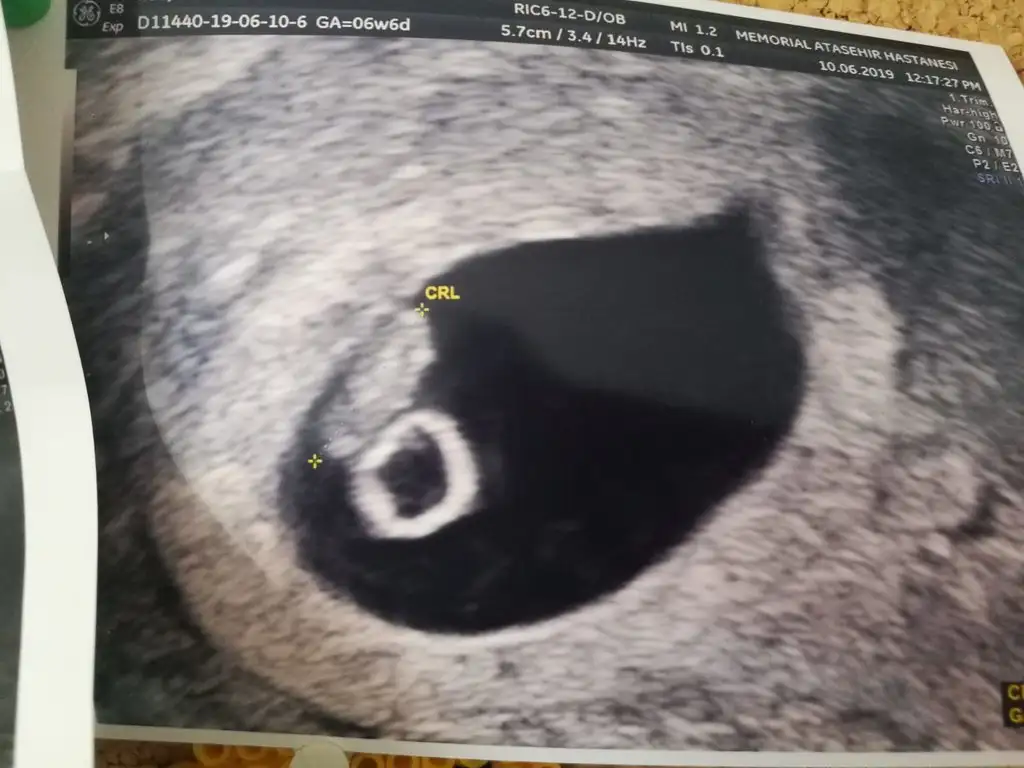

Kız benceEki Görüntüle 2277369 Acaba benim bebişimin Cinsiyeti ne olabilir 8 haftalık Karından

Evet canım sağda duruyor teoriye göre öyleBu teoriye göre bizim kızmı oluyo şimdi arkadaslarkarında usg ile bakıldı

Bu dogrumu canm benim 7 haftalik teoriye solda karinda erkek zaten gissedyrdm dr birgun onceerkek ikili testte kiz dedi anlamadk 14 haftalgm ins degsr9+4 göre erken sekil almış erkek diyorum